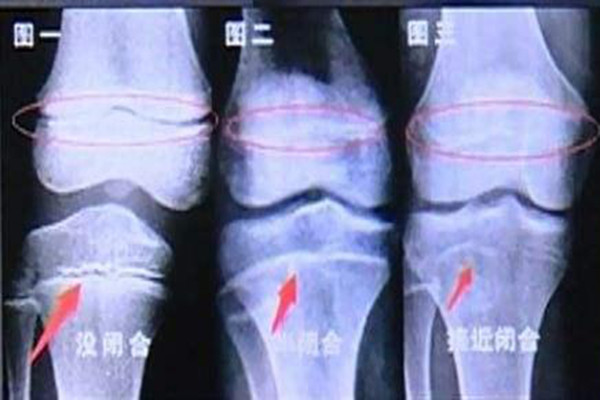

另一方面,肥胖的体型,会压迫骨骼,孩子更容易出现骨骼问题,骨骺线也容易提前闭合,很难长高。